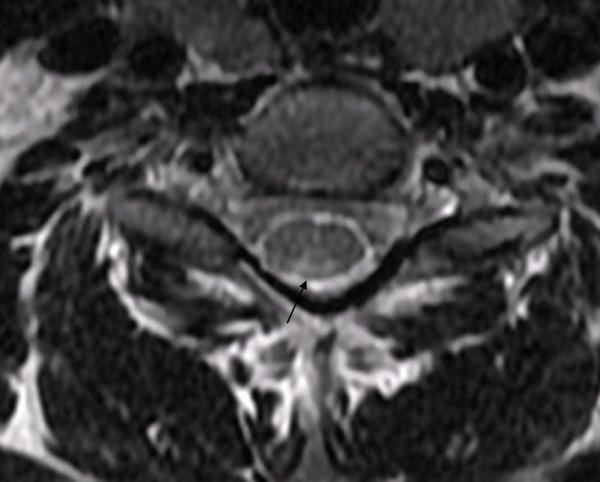

We present a case of cobalamin deficiency in a 29-year-old Moroccan woman who presented with subacute combined degeneration without evidence of anemia or macrocytosis. Magnetic resonance imaging of the spinal cord demonstrated abnormal hyperintense signal changes on T2-weighted imaging of the posterior and lateral columns from the medulla oblongata to the thoracic spine. A diagnosis of subacute combined degeneration of the spinal cord was considered and confirmed by low serum cobalamin. The patient was treated with vitamin B12 supplements and showed improvement in her clinical symptoms.

我们报告一例29岁摩洛哥女性钴胺素缺乏病例,该患者表现为脊髓亚急性联合变性,无贫血或大细胞症证据。脊髓磁共振成像显示,从延髓到胸椎的后柱和侧柱在T2加权成像上有异常高信号改变。考虑诊断为脊髓亚急性联合变性,并通过低血清钴胺素得到证实。患者接受维生素B12补充治疗,临床症状有所改善。